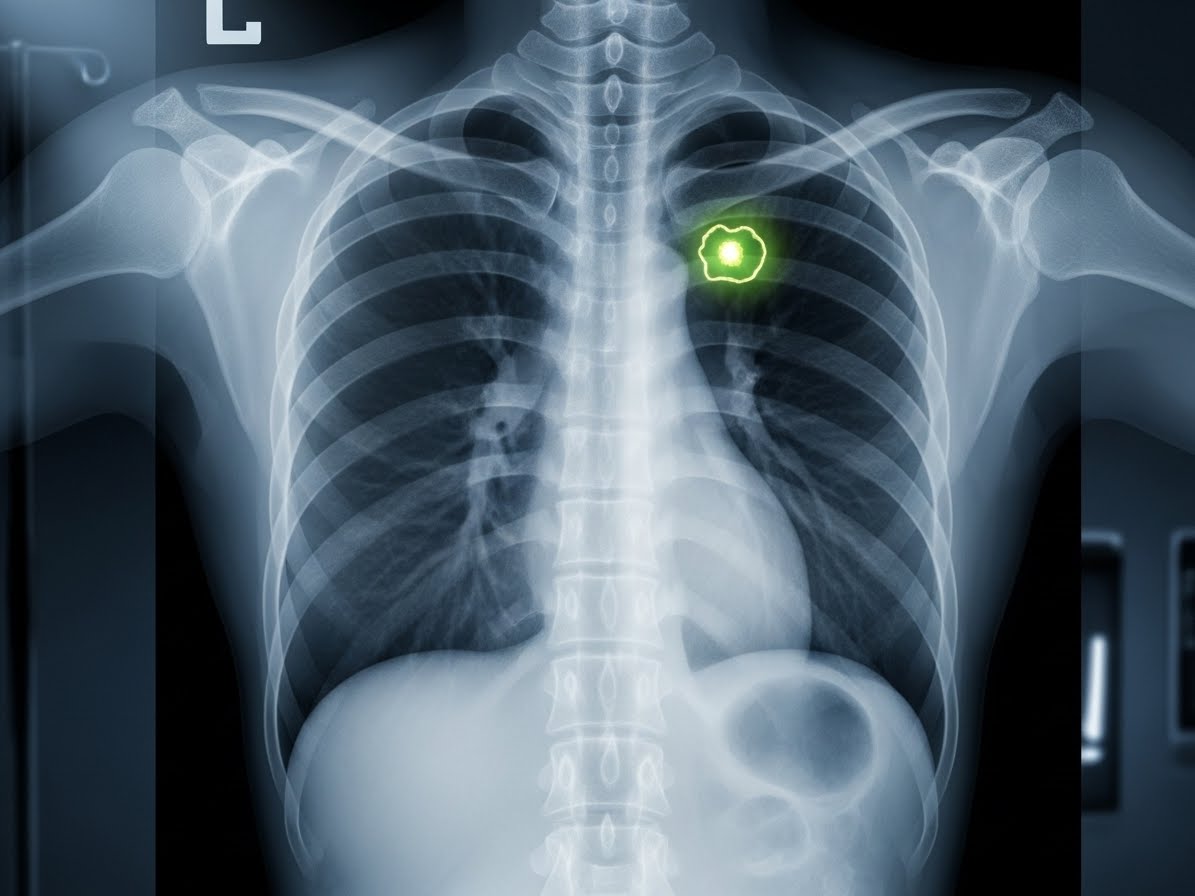

- 흉부 X-ray: 가장 기본적인 검사로, 폐에 이상 소견이 있는지 1차적으로 확인합니다.

- 저선량 흉부 CT: 폐암 조기 진단에 매우 효과적인 검사로, 특히 고위험군(장기 흡연자 등)에게 권장됩니다. 미세한 병변까지 발견할 수 있어요.